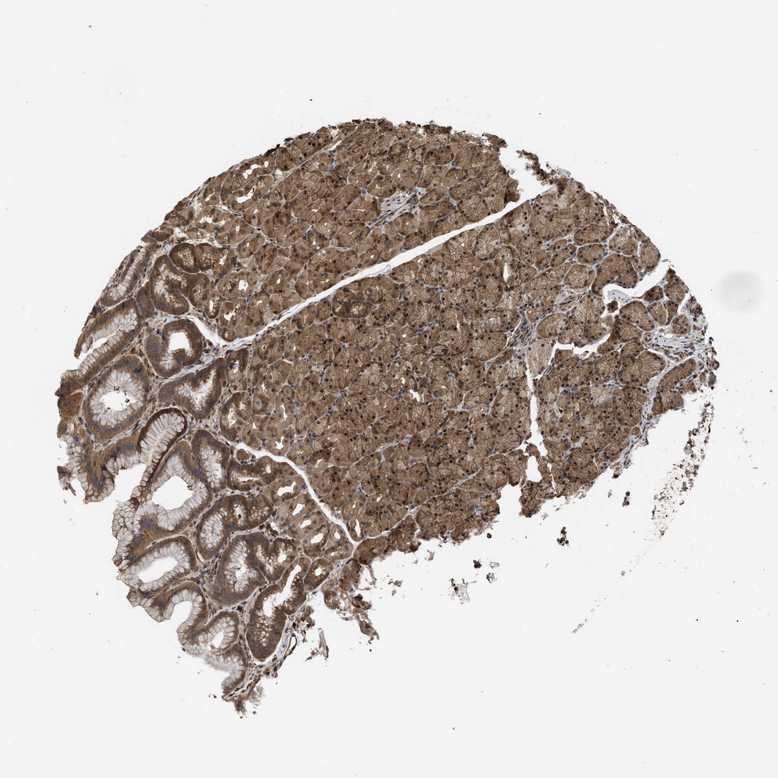

STOMACH 2 - Antibody stainingi

Antibody staining in the annotated cell types in the current human tissue is reported as not detected, low, medium, or high, based on conventional immunohistochemistry profiling in selected tissues. This score is based on the combination of the staining intensity and fraction of stained cells.

Each image is clickable and will lead to virtual microscopy that enables deeper exploration of all samples and also displays staining intensity scores, fraction scores and subcellular localization as well as patient and tissue information for each sample.

Antibody HPA026918Antibody CAB013274Antibody CAB018389

Glandular cells MediumHighMedium